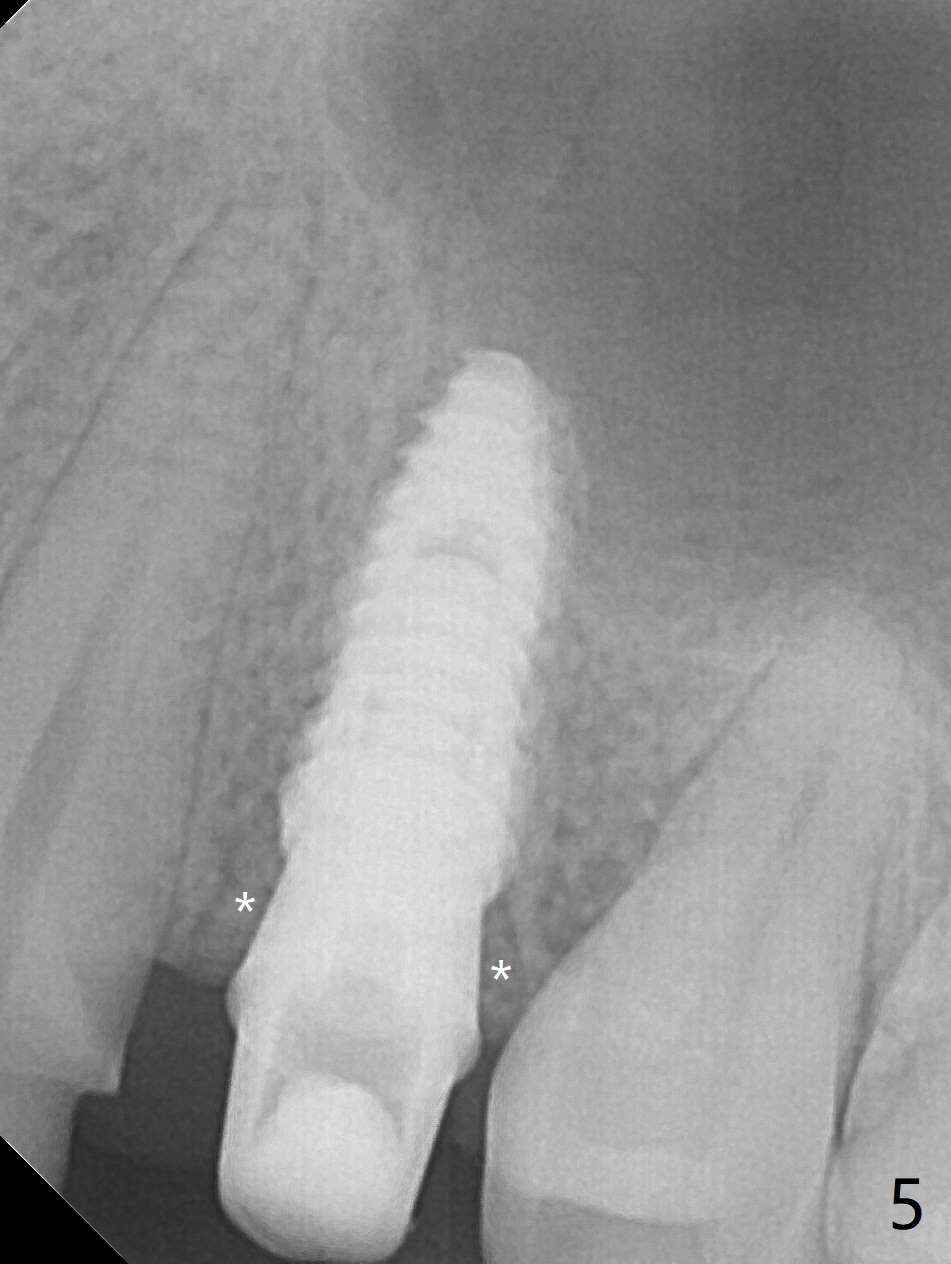

After extraction of the residual roots at #12 and crown prep at #11, osteotomy at #12 is established with Pointed Lindamann bur and 2.2 mm bur for ~ 15 mm. There feels to be sinus floor perforation; a parallel pin is inserted deeper than expected (Fig.1), but there is no membrane perforation. Following sequential osteotomy, a 4x10 mm dummy implant is placed partially with stability (Fig.2). When the same sized definitive implant is placed subcrestally (Fig.3-5 (*: Vera Graft)), the stability remains (~60 Ncm) in spite of the fact that the trajectory is changed once. The coronal socket does not seem to heal 8.5 months postop, in part due to poor hygiene of splinted provisional (Fig.6).